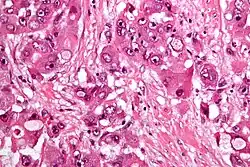

Micrograph of fibrolamellar hepatocarcinoma showing the characteristic laminated fibrosis between the tumor cells with a low NC ratio. H&E stain.

The histopathology of FLC is characterized by laminated fibrous layers, interspersed between the tumor cells. Cytologically, the tumor cells have a low nuclear to cytoplasmic ratio with abundant eosinophilic cytoplasm.[1] Tumors are non-encapsulated, but well circumscribed, when compared to conventional HCC (which typically has an invasive border).